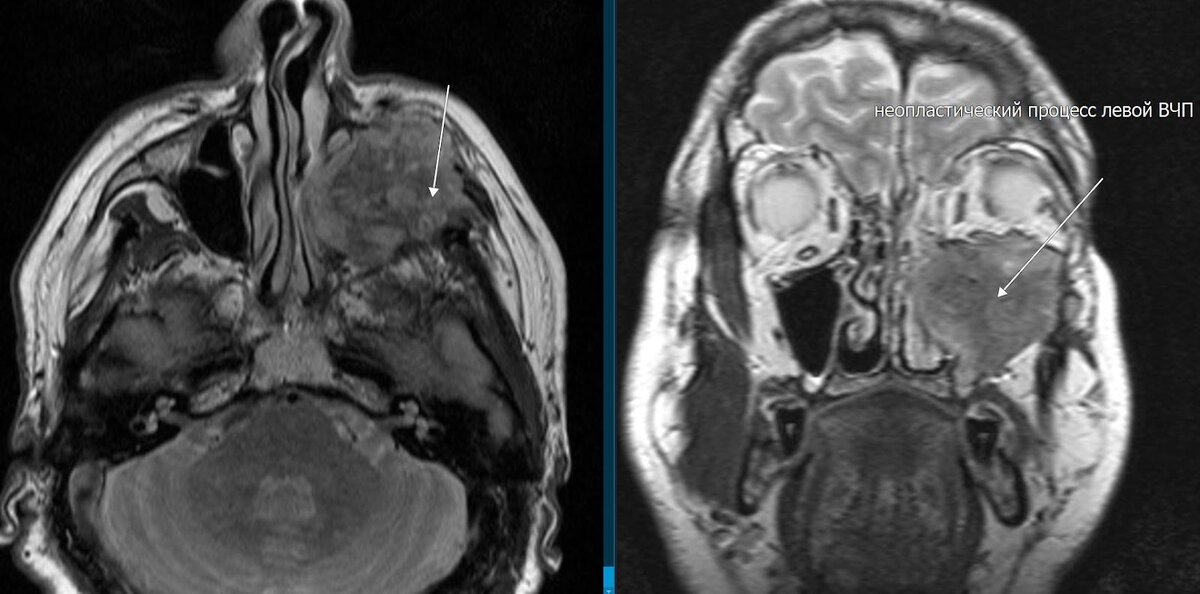

На МРТ был выявлен массивный неопластический процесс (tumor) левой верхнечелюстной пазухи с отсутствием визуализации (деструкцией) стенок и инфильтрацией полости носа, клеток решетчатой кости, клетчатки лицевой области, височной ямки, околобульбарной клетчатки слева и внутричерепным ростом, без инвазии вещества мозга и левого зрительного нерва. Более вероятная инвазия нижней и латеральной прямых мышц левого глазного яблока. Левосторонний экзофтальм.

На рисунке показан внутричерепной рост опухоли, без инфильтрации вещества мозга, околобульбарную клетчатку слева.